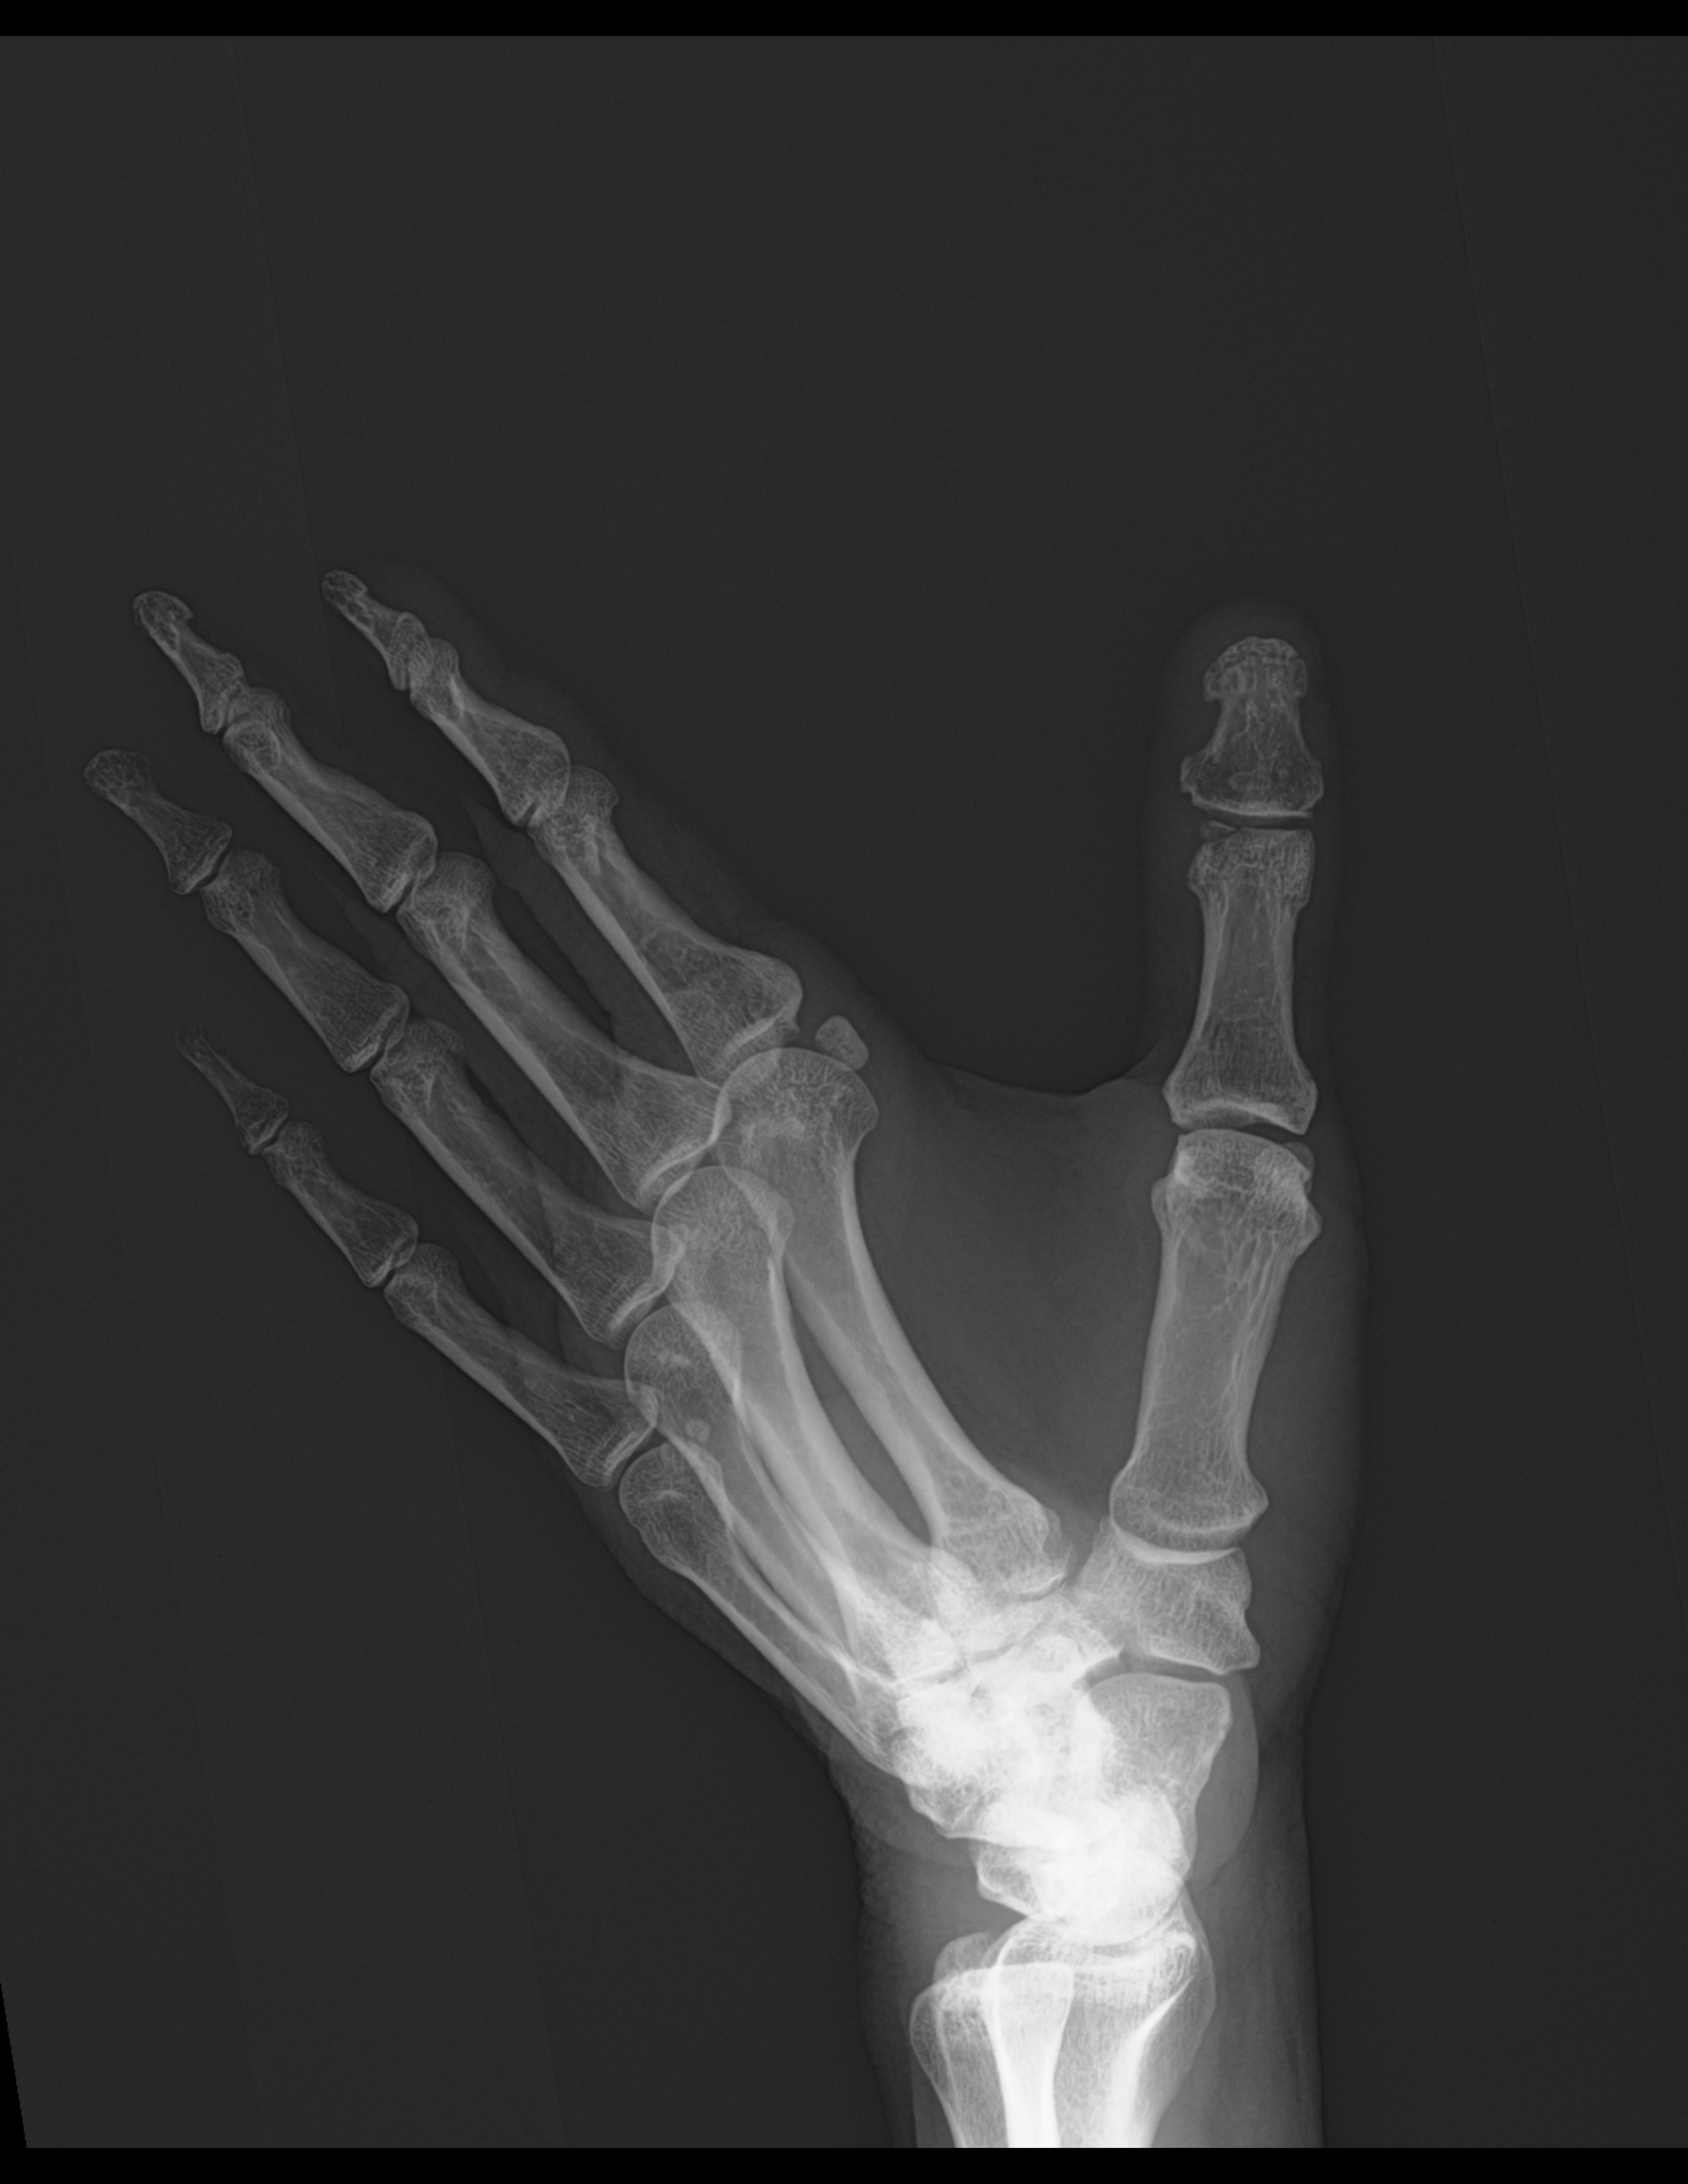

Se realizan radiografías en proyección anteroposterior y oblicua de mano izquierda, donde se observa lo siguiente:

Los tejidos blandos del primer dedo muestran aumento en su volumen. Con presencia de calcificaciones en la superficie palmar de la falange distal del primer dedo.

Se identifica una solución de continuidad cortical en la epífisis distal de la falange proximal del primer dedo.

No se observan lesiones líticas ni blásticas.

Los espacios y superficies articulares muestran adecuada amplitud y alineación.

Estudio radiográfico de mano izquierda con hallazgos que sugieren fractura distal de la falange proximal de del primer dedo.

Edema en los tejidos blandos del primer dedo. Presencia de calcificaciones en la superficie palmar de la falange distal del primer dedo.